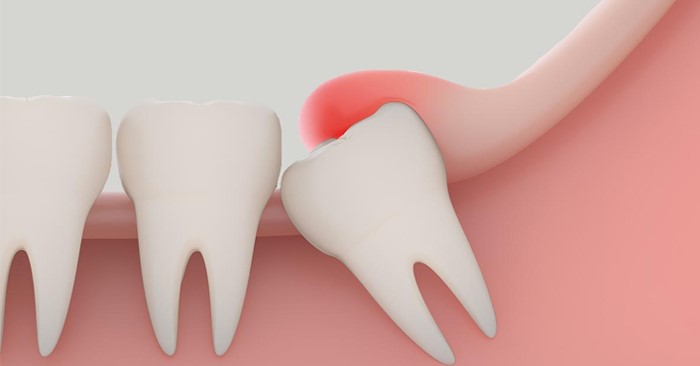

Thông thường, viêm lợi trùm thường xuất hiện ở răng khôn hàm dưới, và tình trạng này có thể ảnh hưởng nghiêm trọng đến sức khỏe răng miệng cũng như dễ phát sinh nhiều biến chứng nguy hiểm. Viêm lợi trùm xảy ra do cung hàm bị thiếu chỗ, khiến cho răng khôn mọc lệch và không thể thoát khỏi vạt nướu bao phủ bên trên. Kết quả là, thức ăn, vi khuẩn và mảng bám dễ dàng bị nhồi nhét và lắng đọng tại khu vực này, dẫn đến nhiễm trùng và sưng tấy.

Lợi trùm răng khôn, hay còn gọi là răng số 8, là tình trạng khi răng khôn chỉ mọc một phần, trong khi phần còn lại bị nướu che phủ hoàn toàn. Vạt nướu này giãn ra và bao quanh bề mặt răng, làm cho thức ăn dễ dàng lọt vào trong và mắc kẹt, gây khó khăn trong việc vệ sinh răng miệng. Ngoài ra, sự tích tụ mảng bám và thức ăn thừa, kết hợp với sự tấn công của vi khuẩn, sẽ thúc đẩy quá trình sản sinh axit, từ đó bào mòn men răng và làm yếu chân răng.

2. Răng khôn mọc lệch: Trong quá trình mọc, nếu không còn đủ chỗ, răng khôn sẽ mọc lệch, ảnh hưởng đến sự phát triển của răng và gây viêm nướu. Điều này không chỉ gây khó chịu mà còn tạo điều kiện cho vi khuẩn phát triển.